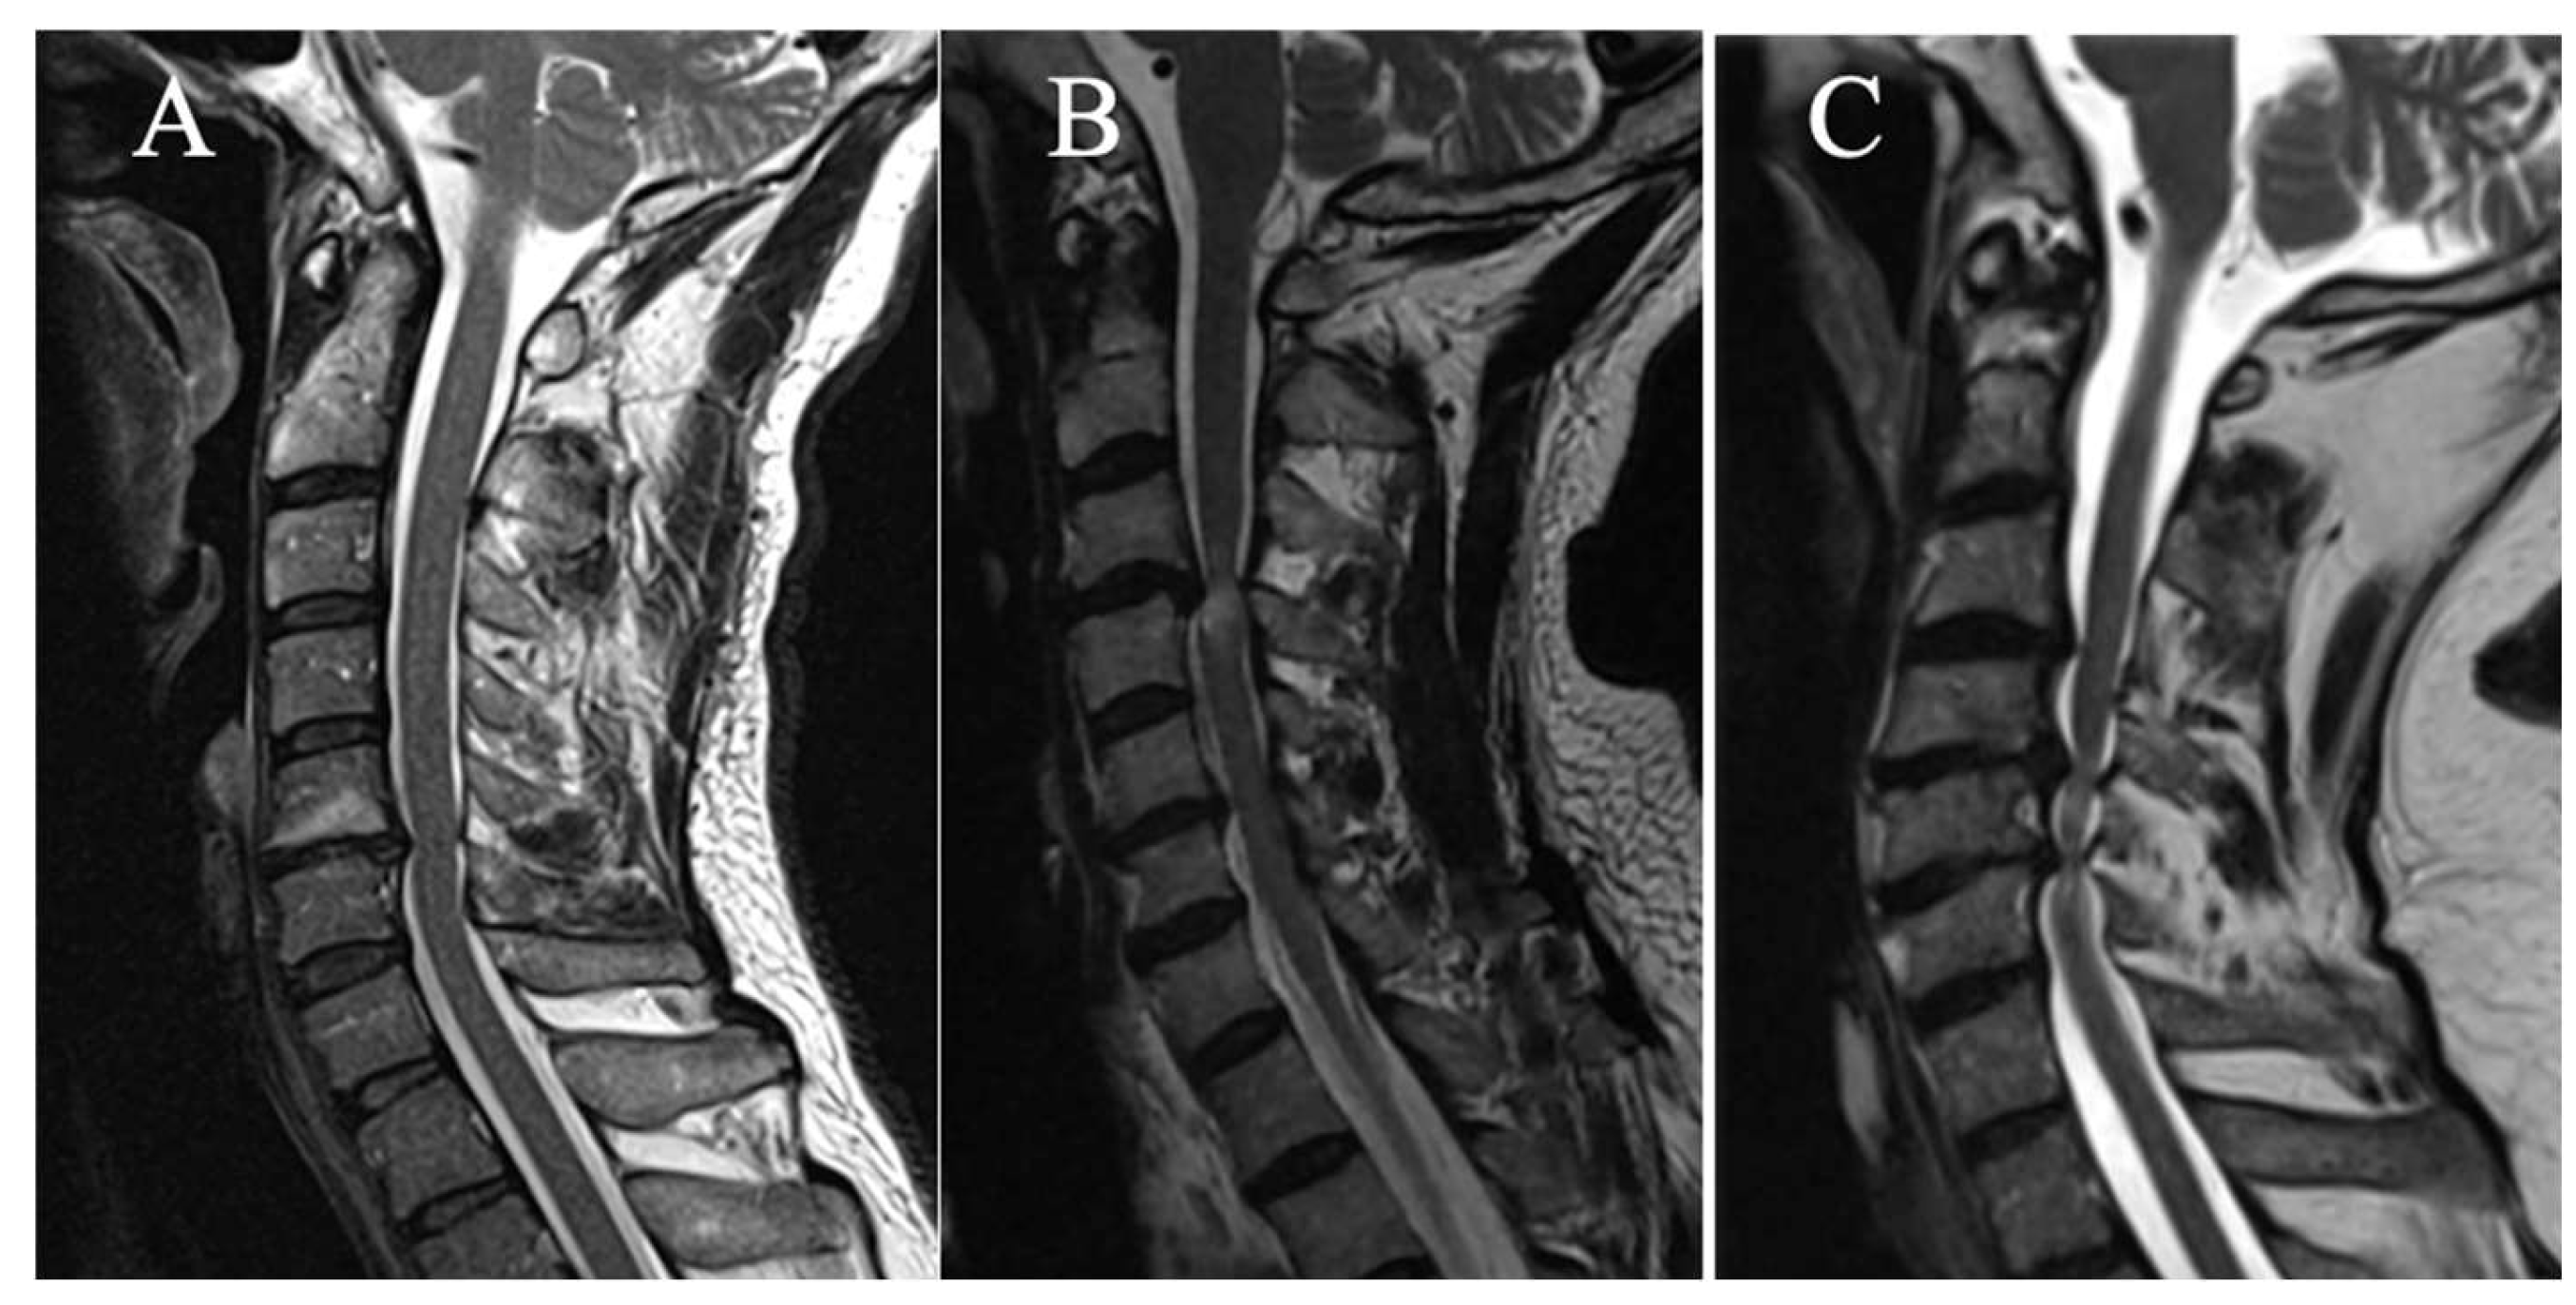

3 grades have been selected on sagittal slice (Figure 2):

(A) No T2HI

(B) Focal T2HI (limited to one intervertebral space and adjacent vertebral bodies)

(C) Multi-segmental T2HI (Extending beyond two intervertebral spaces)

Figure 2. (A) No T2HI ; (B) Focal T2HI ; (C) Multifocal T2HI.